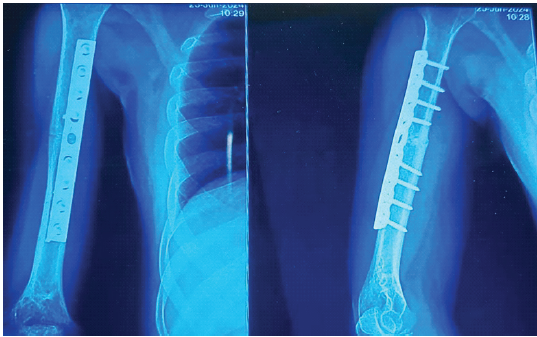

The overall complication rate was 15% (nine patients), and 5% (three patients) required secondary surgery. Nonunion occurred in one patient (AO/OTA 12 A3) in the MIPO group and two patients (AO/OTA 12A3 and 12B3) in the ORPO group who underwent secondary surgical intervention (Figs. 5A and 5B). Other complications in the post-operative period included distraction in 3.33% (2 patients in Group A) and RN palsy in 6.67% (4 patients in Group B). Hematoma, infection, delayed union, malalignment, irritation due to implants, or screw pullout did not occur.

Fig. 5: Nonunion requiring secondary surgical interventions. (A) Anteroposterior and Lateral radiographic images of the right humerus taken 6 months after 10-Hole LCP Fixation exhibiting biomechanical failure, marked by evident distraction, inadequate bridging of the fracture and lack of callus formation (R=right). (B) AP and lateral radiographic views after using a 9-hole DCP in the right humerus also demonstrated no signs of osseous healing, and a gap was still evident at six months.

9-hole DCP in the right humerus also demonstrated no signs of osseous healing, and a gap was still evident at six months.